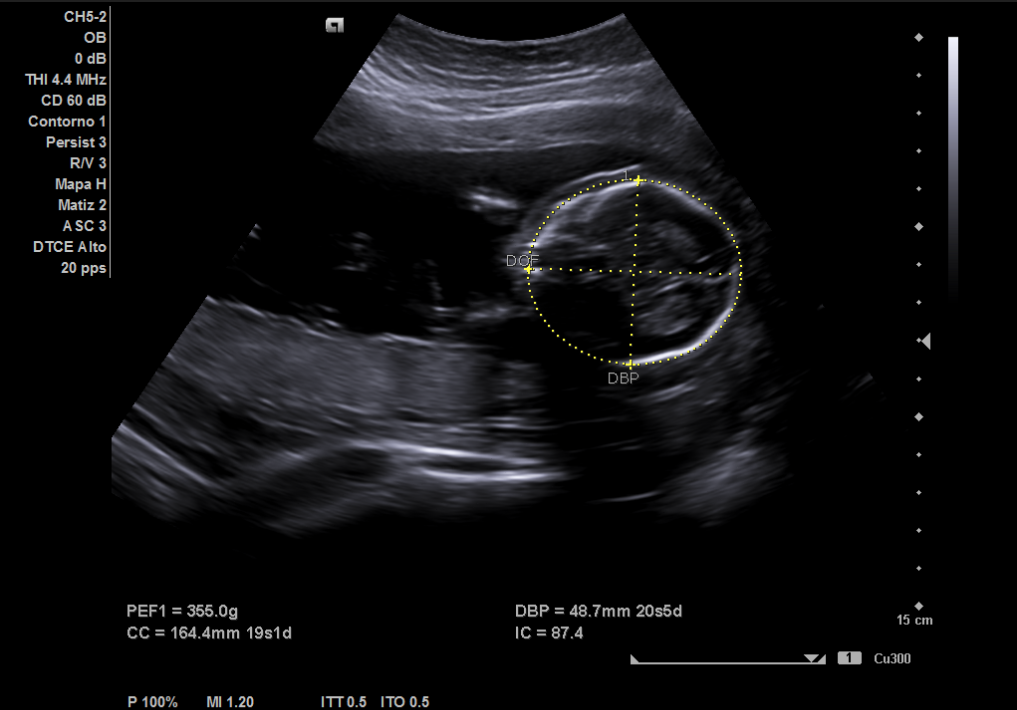

Ecografía: posición fetal con cabeza hacia la izquierda, bolsa más profunda de líquido amniótico de 7 centímetros, actividad cardíaca fetal normal (imagen 3), placenta ubicada en posición anterior, feto único. Se realiza medición de perímetro cefálico y diámetro biparietal (imagen 1) usando software de ecógrafo, así como del perímetro abdominal (imagen 2), estimando una edad gestacional entre 19 semanas y 1 día (cefálico) y 20 semanas y 3 días (abdominal).

Gestación normal. La ecografía realizada por Ginecología confirma una edad gestacional de 20 semanas y 1 día, realizada ese mismo día.